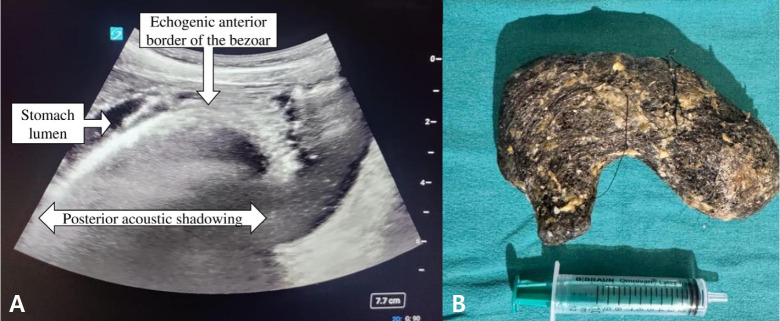

Abdominal pain in a young girl: a twist in the tale.